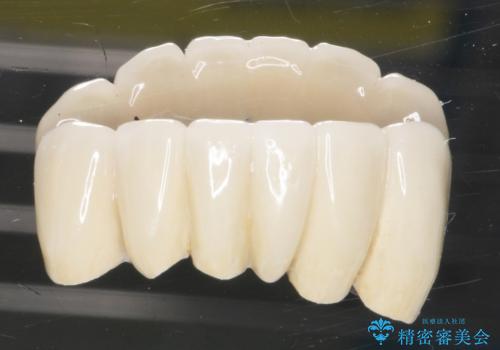

再生療法から1年後リエントリー手術により骨の再生を確認し、骨外科処置(骨を平らにして歯周ポケットの根本的な改善を図る処置)を行ったのち、連結補綴を行いました。

歯も神経も残したいという患者様のご希望により、補綴前に部分矯正を行っております。

生活歯(神経が生きている歯)のため形成量(歯を削合できる量)に限界がありましたが、熟練の技工士さんの素晴らしい技術により補綴を行うことができました。

クラウンの種類:メタルボンドクラウン エコノミー